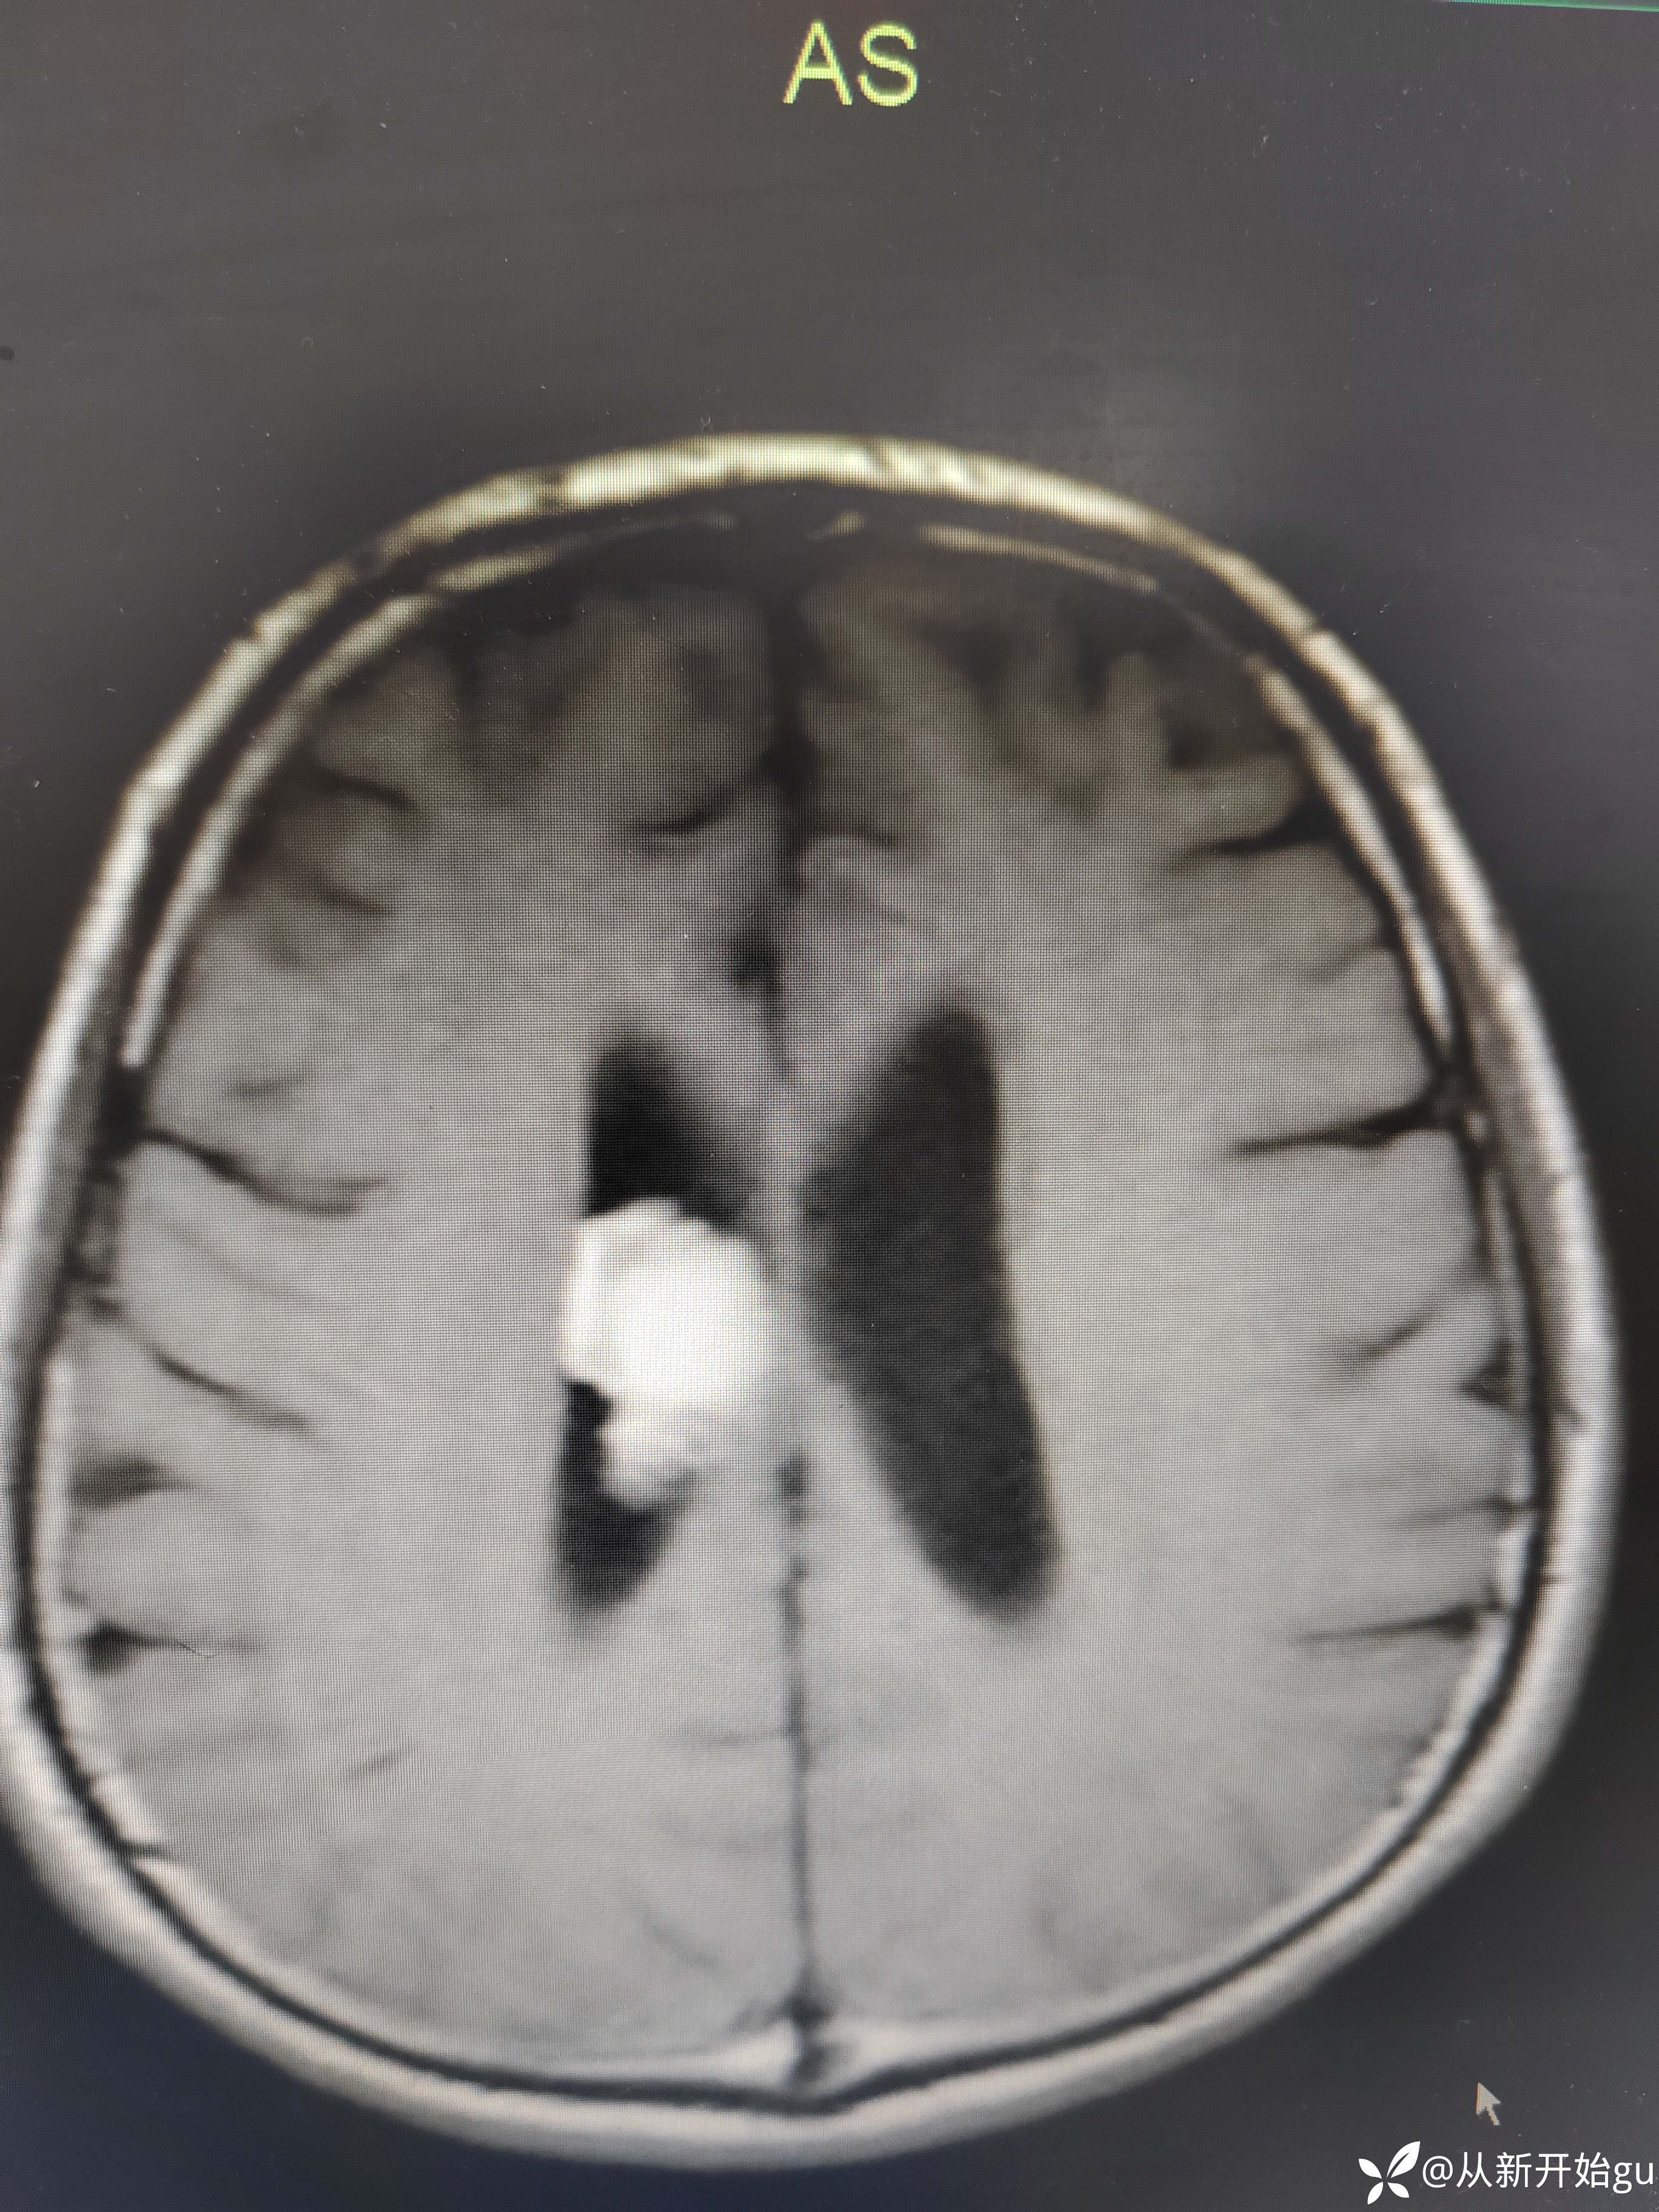

T1

T1